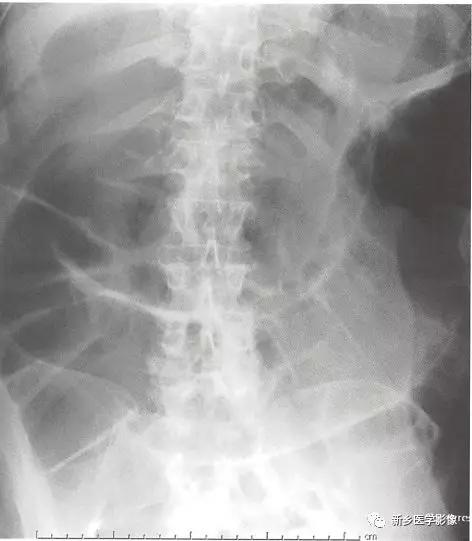

机械性肠梗阻:小肠梗阻(SBO)

1、病理生理学: 存在一种小肠内部或外部的病变阻塞肠腔。随着时间推移,由于连续吞下的气体和持续由胃、胰腺、胆道系统和小肠产生的肠液充满肠腔,小肠肠腔将从梗阻点向近端肠道逆行性逐渐扩张。

为了克服梗阻,肠道将持续蠕动或增加。这可导致高亢、活跃的肠鸣音。随着时间推移,蠕动波将推动梗阻远端的小肠和结肠内容物向前移动。如果是完全性肠梗阻,在出现症状足够长时间后,直肠或乙状结肠内通常见不到气体影。

传统X线平片上,梗阻点近端可见多个扩张的小肠肠襻(>2.5cm)。

在直立位或侧卧位片上,在梗阻近端小肠通常可见多个气-液平面。

如果时间足够长,梗阻远端的肠道内容物可完全排出,则在结肠尤其是直肠内只有很少或完全见不到气体影。